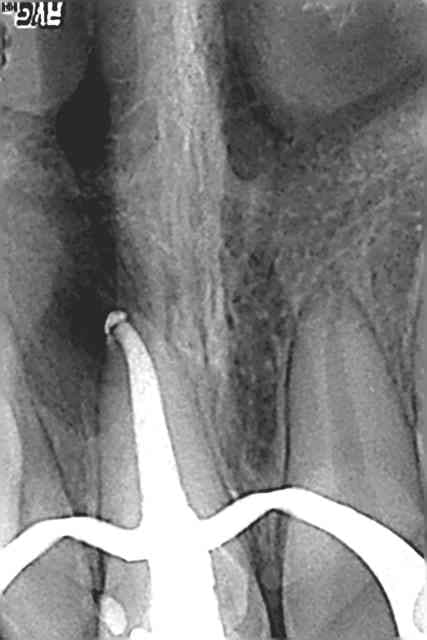

Les points négatifs pour le pronostic :

- Nécrose initiale (donc présence de bactéries +++) et lésion osseuse associée

- Hygiène de la patiente moyenne (ado)

- son age. Sa dent durera t elle toute sa vie ?

- Obturation coronaire au composite (dont on connait la durée de vie relative...)

Après je suis content de mon traitement. Je ne maitrise pas la chir endo, je n'ai pas le matériel pour le MTA/IRM/Super EBA non plus, mais au moins je saurai que dans un tel cas, c'est mieux ! Merci tout le monde

dis toi bien qu'au mieux tu fais du "transitoire de longue durée". wait and see.

Une dent qui a subit un traumatisme comme ici qui a engendré une nécrose et ensuite une lésion péri apicale, endo... Cela fait déjà beaucoup. De plus il va y avoir une reconstruction prothétique par dessus avec surement un inlay core ou un composit post et couronne si le compo se fracture mais que la racine reste ok..

Donc wait and see mais commencer à parler a la patiente de la solution implantaire, mettre les sous de côté, on sait jamais...

Joli travail, equipe toi de limes de plus de 50 car il n est pas rare d aller jusqu a 70 sur certaines incisives centrales ou canines bien larges et longues. La derniere canine de memoire, j étais à 35mm ( j avais peur d aller finir dans l'oeil) et preparation jusqu a lime 70..